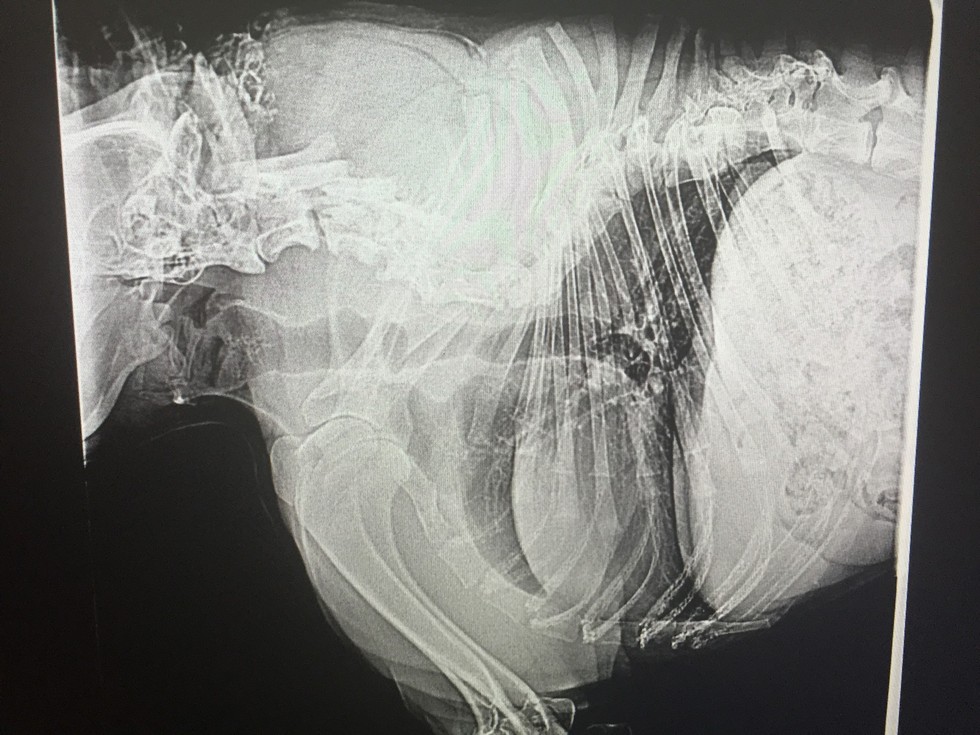

Quasimodo est un chienunique en son genre. Cet adorable Berger Allemand est atteint d'une affection génétique rarissime : le "short spine syndrome" (en Français : "syndrome de la petite colonne vertébrale").

Une maladiequi a entraînéune déformation irréversible de la colonne et l'empêche de se mouvoir normalement ou de tourner la tête.Quasimodo vient d'être retrouvé par un refuge du Minnesota (États-Unis) alors qu'il errait dans les rues. Un collier trop petit lui enserrait le cou, la peau avait même commencé à le recouvrir. Un signe clair que le chien était livré à lui-même depuis un certain temps.

C'est l'association Second Hand Houndsqui a pris en charge Quasimodo et qui l'a baptisé ainsi en clin d'oeil au personnage du Bossu de Notre-Dame.Les vétérinaires ont estimé qu'il était âgé d'environ quatre ans. Bien sûr, en raison de son affection, Quasimodo est beaucoup plus petit qu'un Berger Allemand adulte.

Des examens plus poussés ont également révélé que l'ossature de sa queue était vrillée et qu'elle interférait avec ses fonctions vitales. Un problème qui sera corrigé prochainement par une intervention chirurgicale.